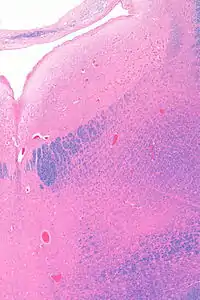

Micrograph showing the locus coeruleus (upper-right of image) in an axial section of the pons. The fourth ventricle (quasi-triangular white area) is in the upper-left of the image. The midline is seen on the left. The large white area in the upper-left corner is where the cerebellum would be. HE-LFB stain.